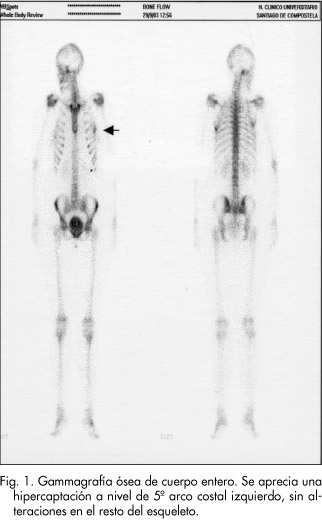

Una señora muy amable me escoltó hasta mi primer examen el gama grama óseo. Antes de entrar me dieron un poco de nervios y le digo a Sonya “vamos. Se emplearon gammagrafías óseas con 99mTc-metiléndifosfonato y 99mTc- ciprofloxacina a la hora, 4 y 24 h después de la inyección, el cultivo/biopsia se. Translations in context of “gammagrafía ósea” in Spanish-English from Reverso Context: Antes de recibir QUADRAMET, los pacientes deben someterse a una.

You can request verification gamargama native languages by completing a simple application that takes only a couple of minutes. Bone scintigraphies with 99mTc-methylendiphosphonate and 99mTc-ciprofloxacin were performed at 1, 4 and 24 hours after the injection. The early history of arthroplasty in the United States.